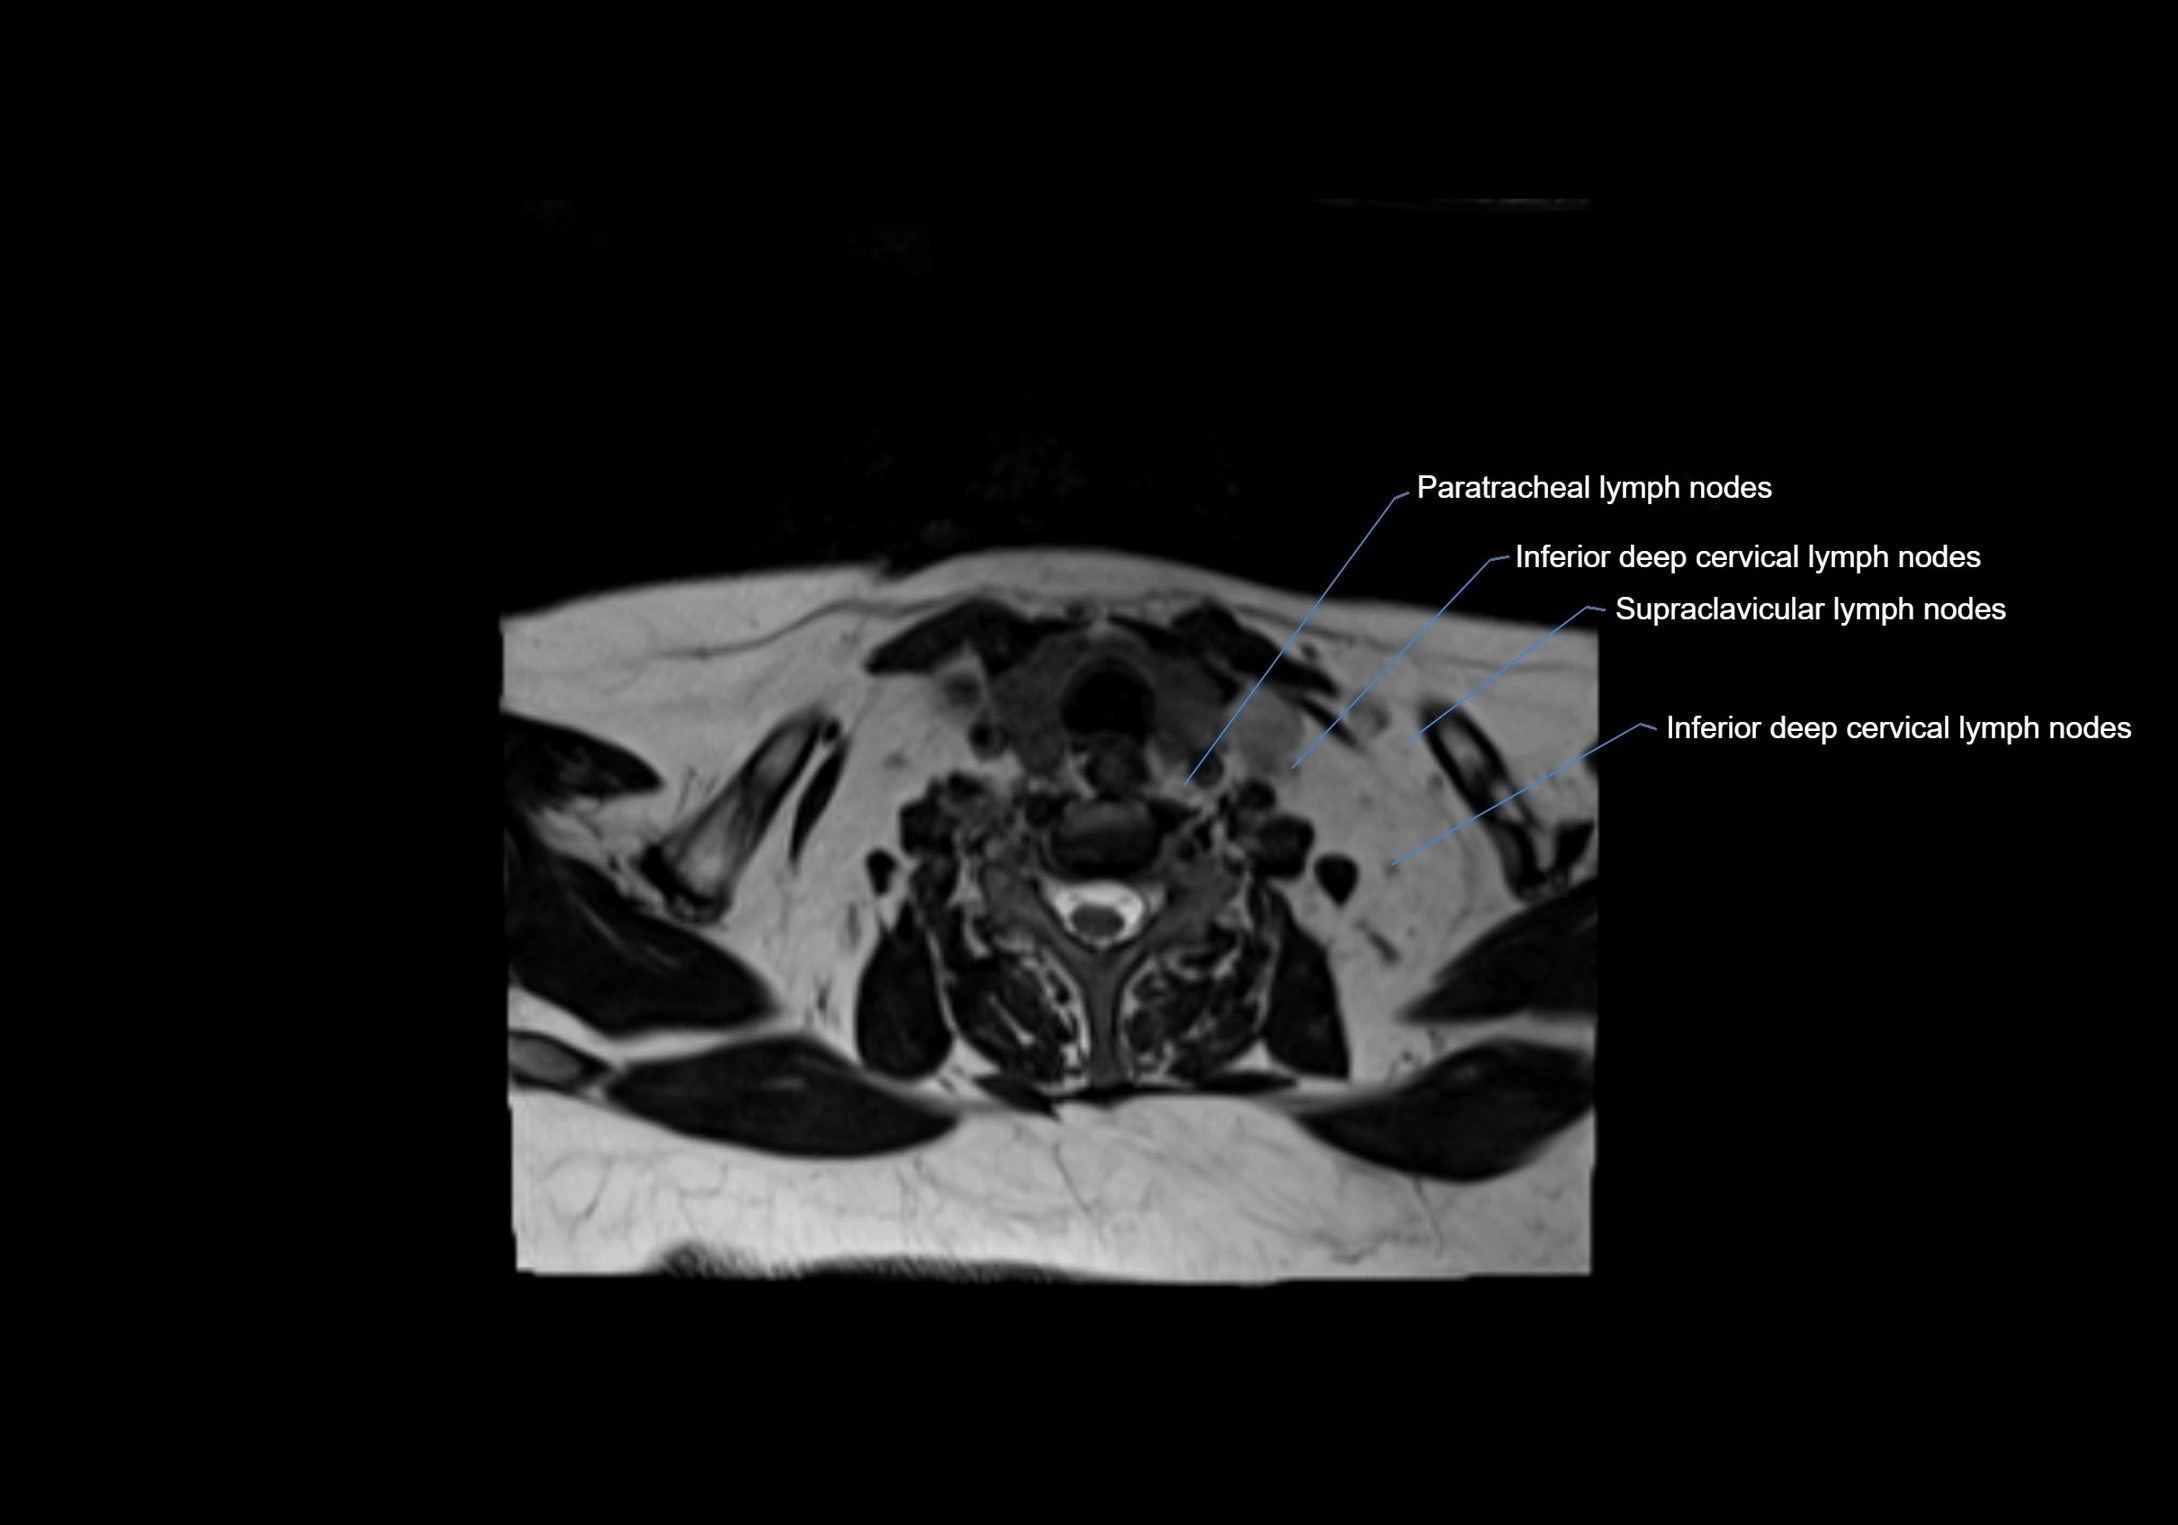

Location

• Found along primary lymph node chains, including preauricular, submandibular, parotid, and occipital regions

• Embedded in subcutaneous fat or superficial fascia, often lateral or posterior to primary nodes

• Variable in number; may occur unilaterally or bilaterally, depending on individual anatomy